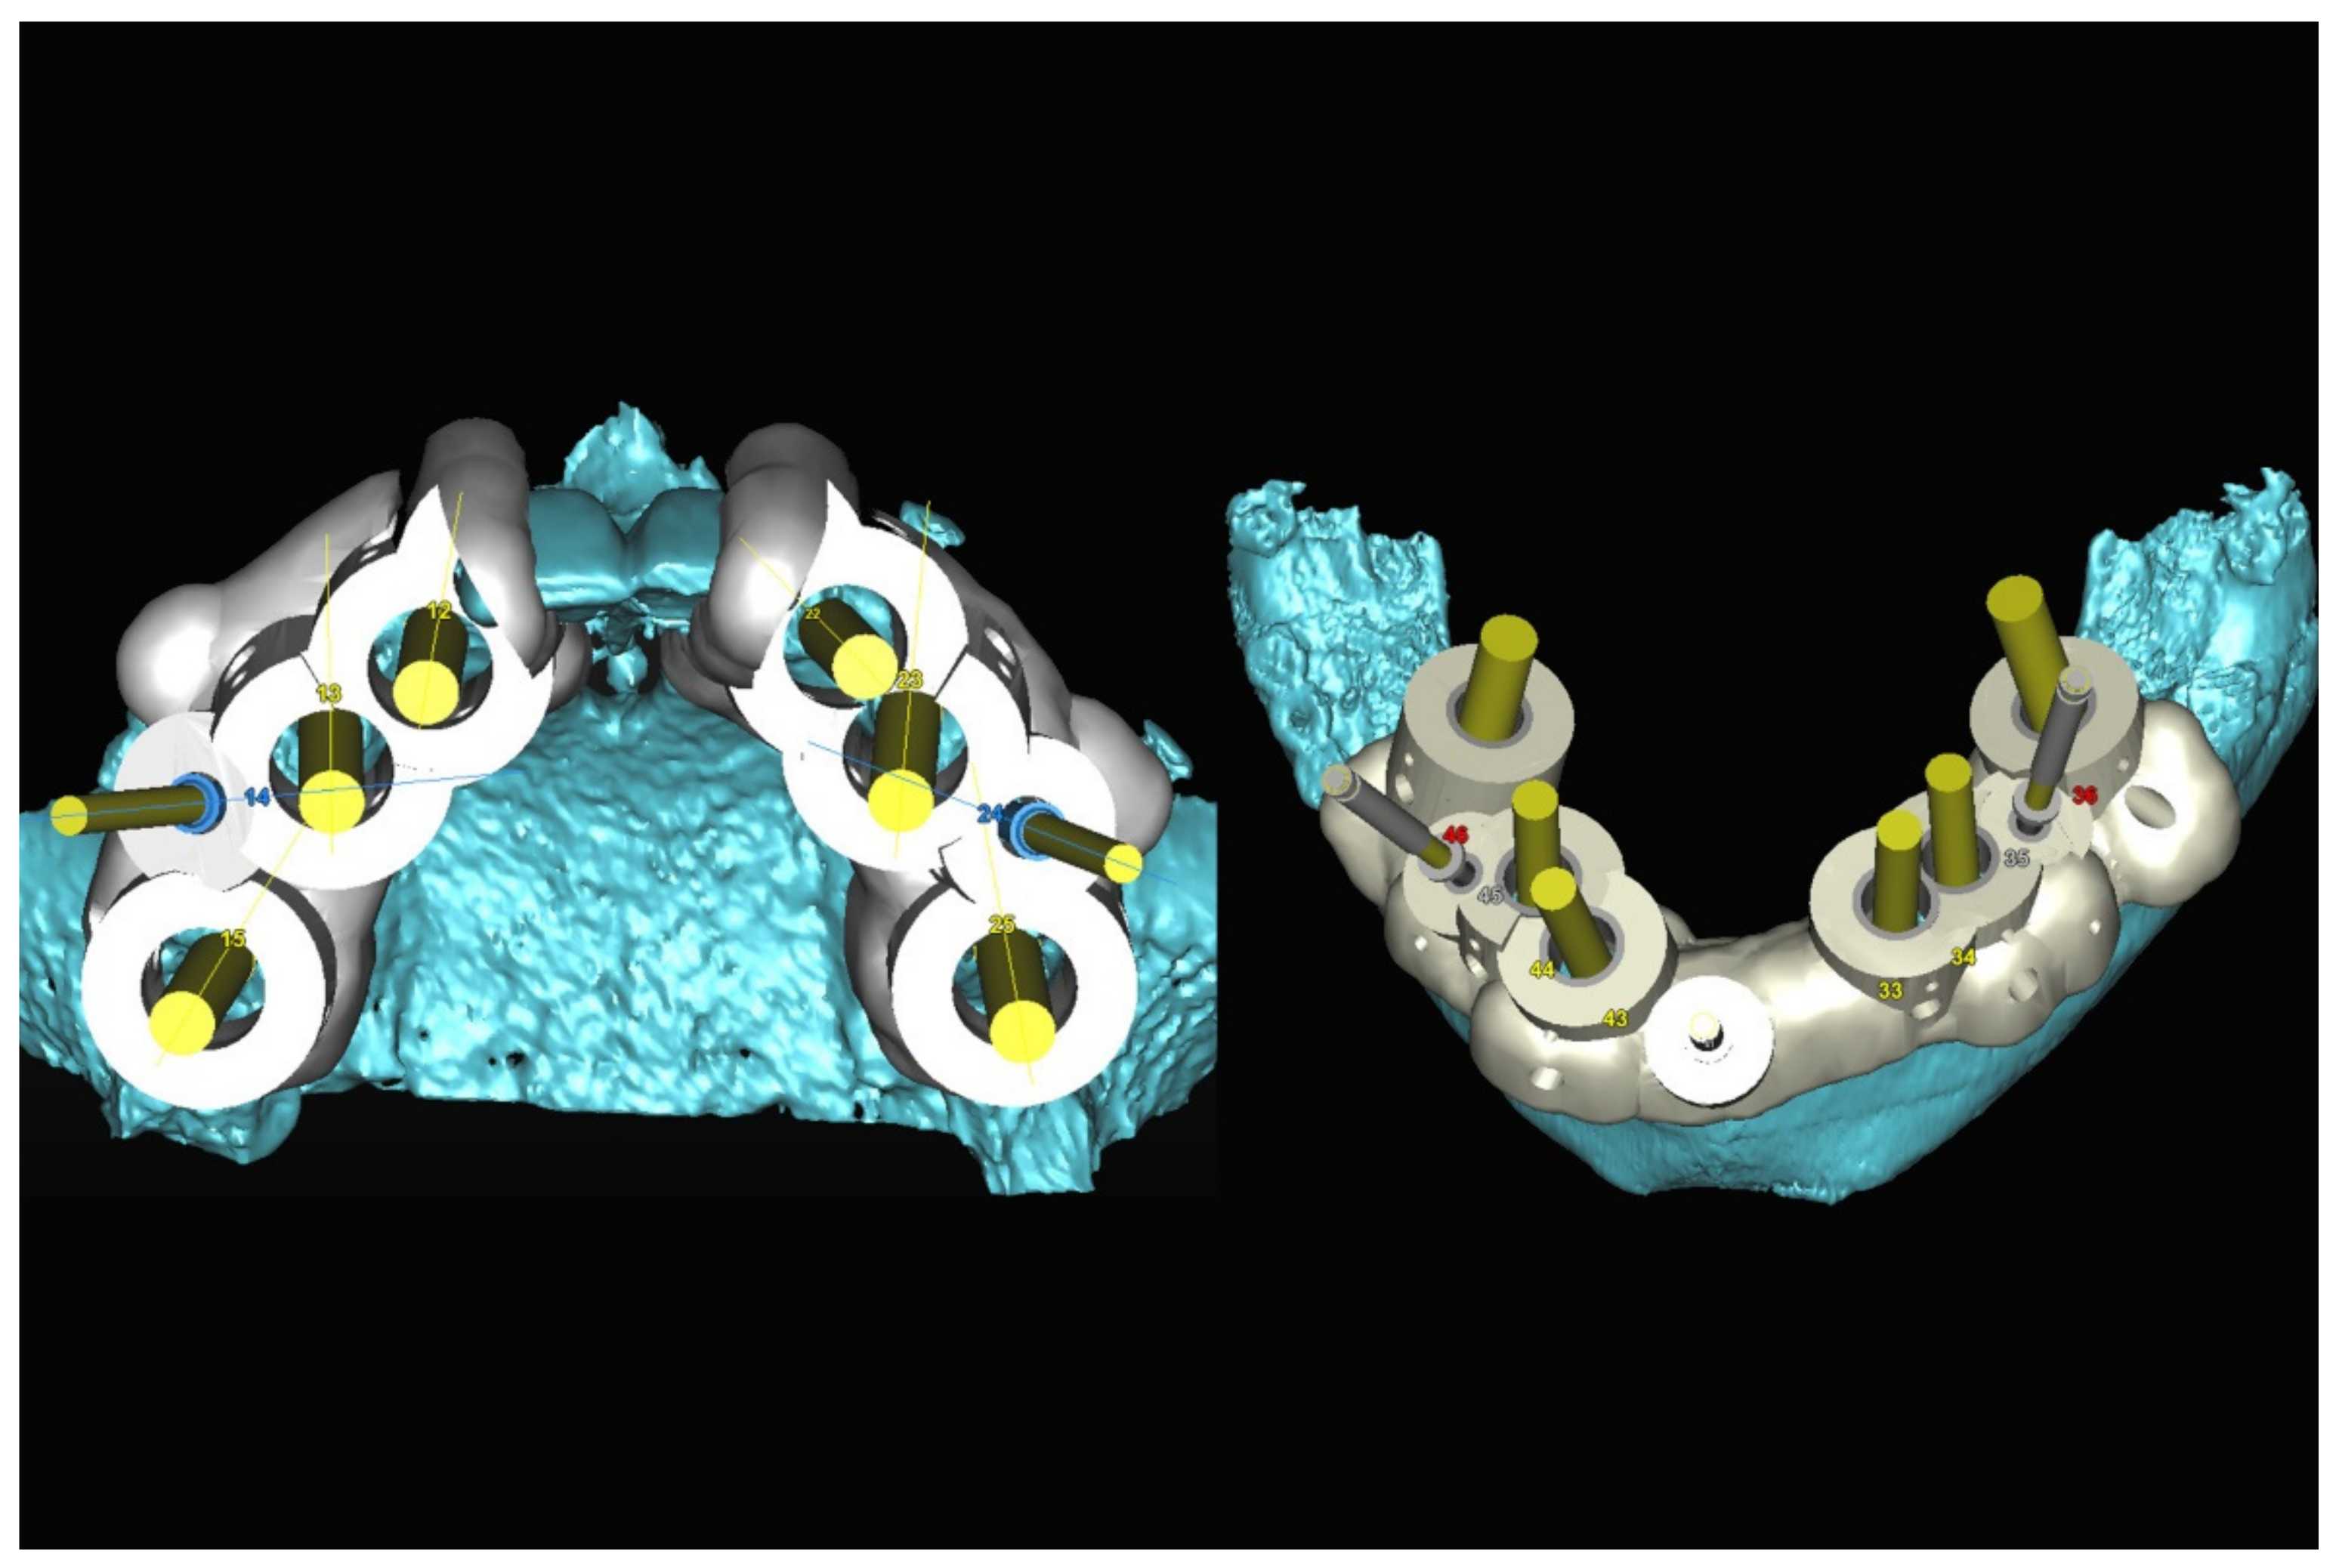

The number, the length, the diameter and the placement of computational virtual implants were determined with respect to the design of the final prosthesis the available residual bone volume and the anatomical limitations according to the previously described technical procedure (Figure 16, Figure 17, Figure 18, Figure 19, Figure 20 and Figure 21).

Figure 18.

Three-dimensional (3D) planning of the number, the diameter and the axis of dental implants with respect to the design of the final virtual maxillary prosthesis.

Figure 19.

Figure 20.

Maxillary and mandibular virtual surgical drilling guides designed according to the implant position.

Figure 21.

Final maxillary and mandibular stereolithographic surgical drilling guides.

6.2.4. Intra-Operative Documentation:

In March 2013, twelve guided dental implants were placed at sites # 12, # 13, # 15, # 22, # 23, # 25, # 33, # 34, # 36, # 43, # 44, and # 46 (Figure 22, Figure 23, Figure 24, Figure 25 and Figure 26)